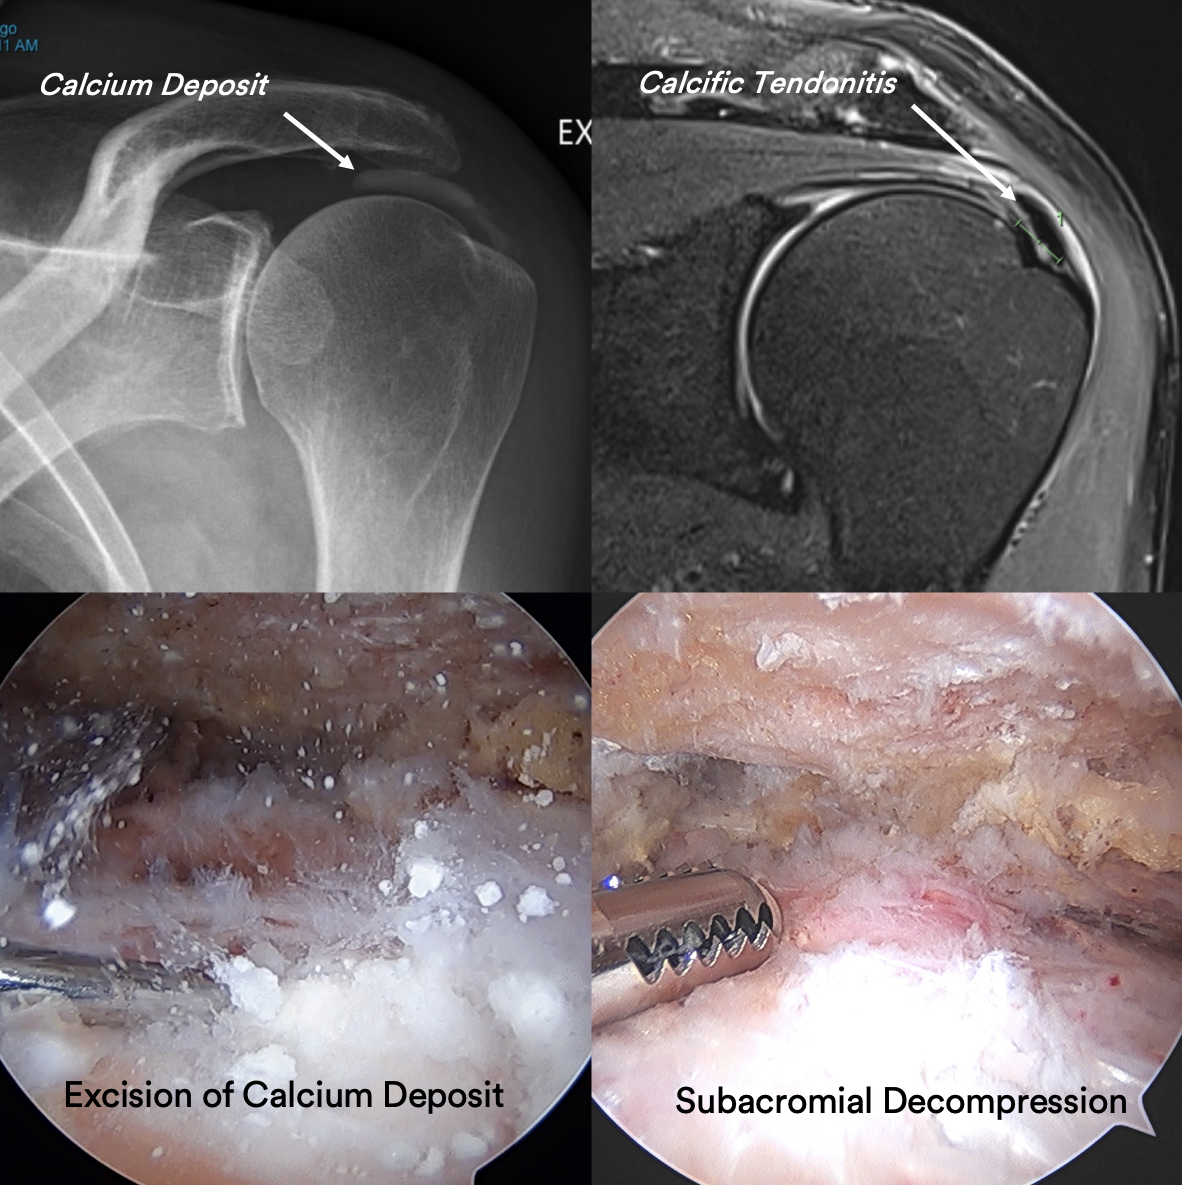

Struggling with persistent shoulder pain? Discover effective treatments for calcium deposits in shoulder joints, known as calcific tendinitis. Learn about common symptoms, non-surgical relief options, and physical therapy exercises to manage chronic inflammation and restore mobility. Expert advice to help you understand this condition and find the right path toward lasting shoulder pain relief and recovery.

Read full article: Calcium Deposits In Shoulder